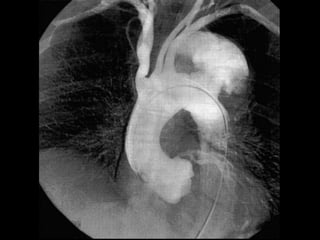

CANDER DE ESOFAGO

ANEURISMA

QUISTE PERICARDICO